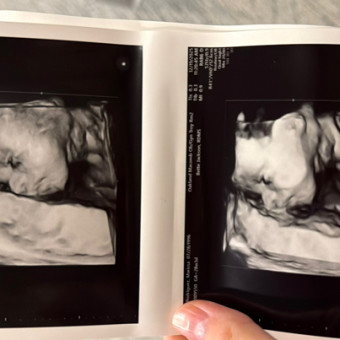

Marissa&Keen- Baby Boy Merideth